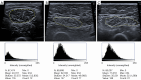

B-mode ultrasound transverse scan images of the rectus femoris muscle in a healthy 17-year-old female with preserved muscle architecture and echogenicity (A); a healthy 83-year-old female (B), and a healthy 68-year-old female (C), both exhibiting a moderate grade 2 of muscle degeneration (moderate/partial loss of muscle architecture and increased echogenicity). Muscle EI in grayscale and histographic analysis was performed using ImageJ software. The young healthy subject (A) demonstrated low EI. The middle-aged subject (C) with moderate muscle degeneration exhibited higher EI compared to the older subject (B). EI, echo intensity.